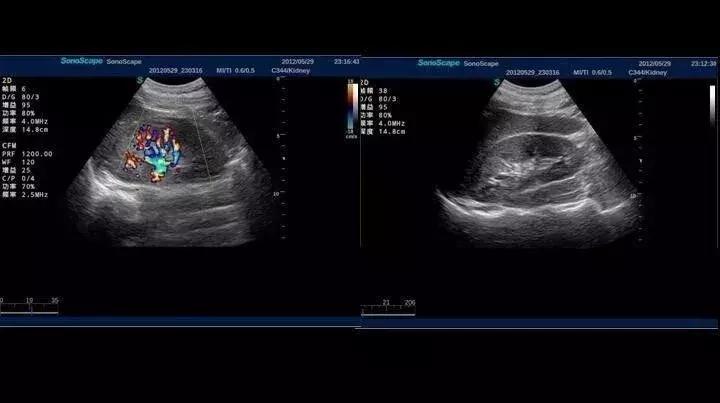

5、为什么“彩超”显示的图像是黑白的?

答:彩超的全名是彩色多普勒超声,简单来说,彩超是在B超的基础上增加了彩色多普勒技术,它可以显示器官、组织的血流情况,根据血流的方向显示为红色或蓝色,而器官、组织或病灶的二维结构信息仍以灰度(黑白)的形式显示在屏幕上。也就是说,普通B超可以显示病变的形态和内部结构,而彩超则可以检测出这些器官的血流灌注情况,可以更好的帮助检测各器官的前期病变。